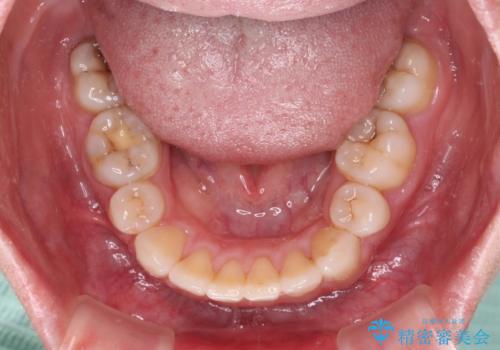

元々上下正中の位置はずれていましたが、治療中によりズレが大きくなったので、元の位置に戻すため治療期間を余計に要しました。

横顔の印象が大きく改善され、患者様には大変満足していただきました。